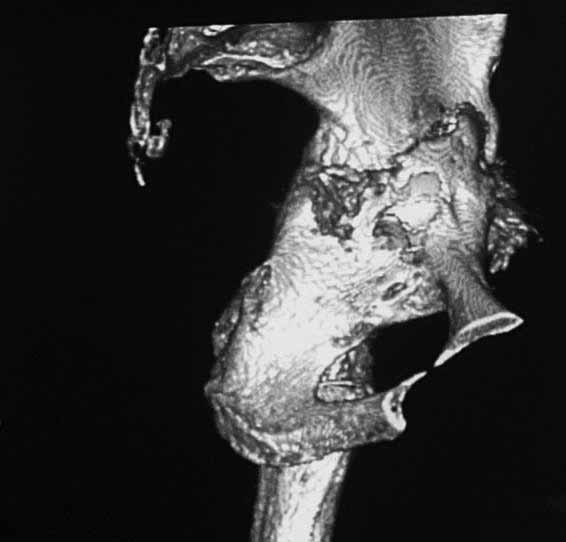

Уважаемые коллеги. Хотелось бы услышать мнения и советы по представляемому случаю.

матки по поводу лейомиомы больших размеров. Несколько месяцев назад появились боли в

области левого тазобедренного сустава. При рентгеновском и КТ исследованиях (июль с.г.)

нестабильность тазового компонента. От предложенной замены протеза пациентка на тот

момент, слава богу, отказалась. Через какое то время боли в области левого тазобедренного

Вопросы: -правильно ли я расцениваю

переломы как стрессовые на фоне неполноценного таза (pelvic insufficiency stress

fractures)?

-Можно ли так же расценить ситуацию на стороне протеза и, соответственно, не

торопиться с ревизией, рассчитывая на вторичную стабилизацию? Уж больно не хочется менять

ножку.

-Если думать о ревизии, то когда? На представленных снимках тазобедренный сустав до и

сразу после операции, затем 2 снимка 2009г., когда ничего не беспокоило, затем КТ 2-х

месячной давности и вчерашние рентгенограммы обоих тазобедренных суставов.